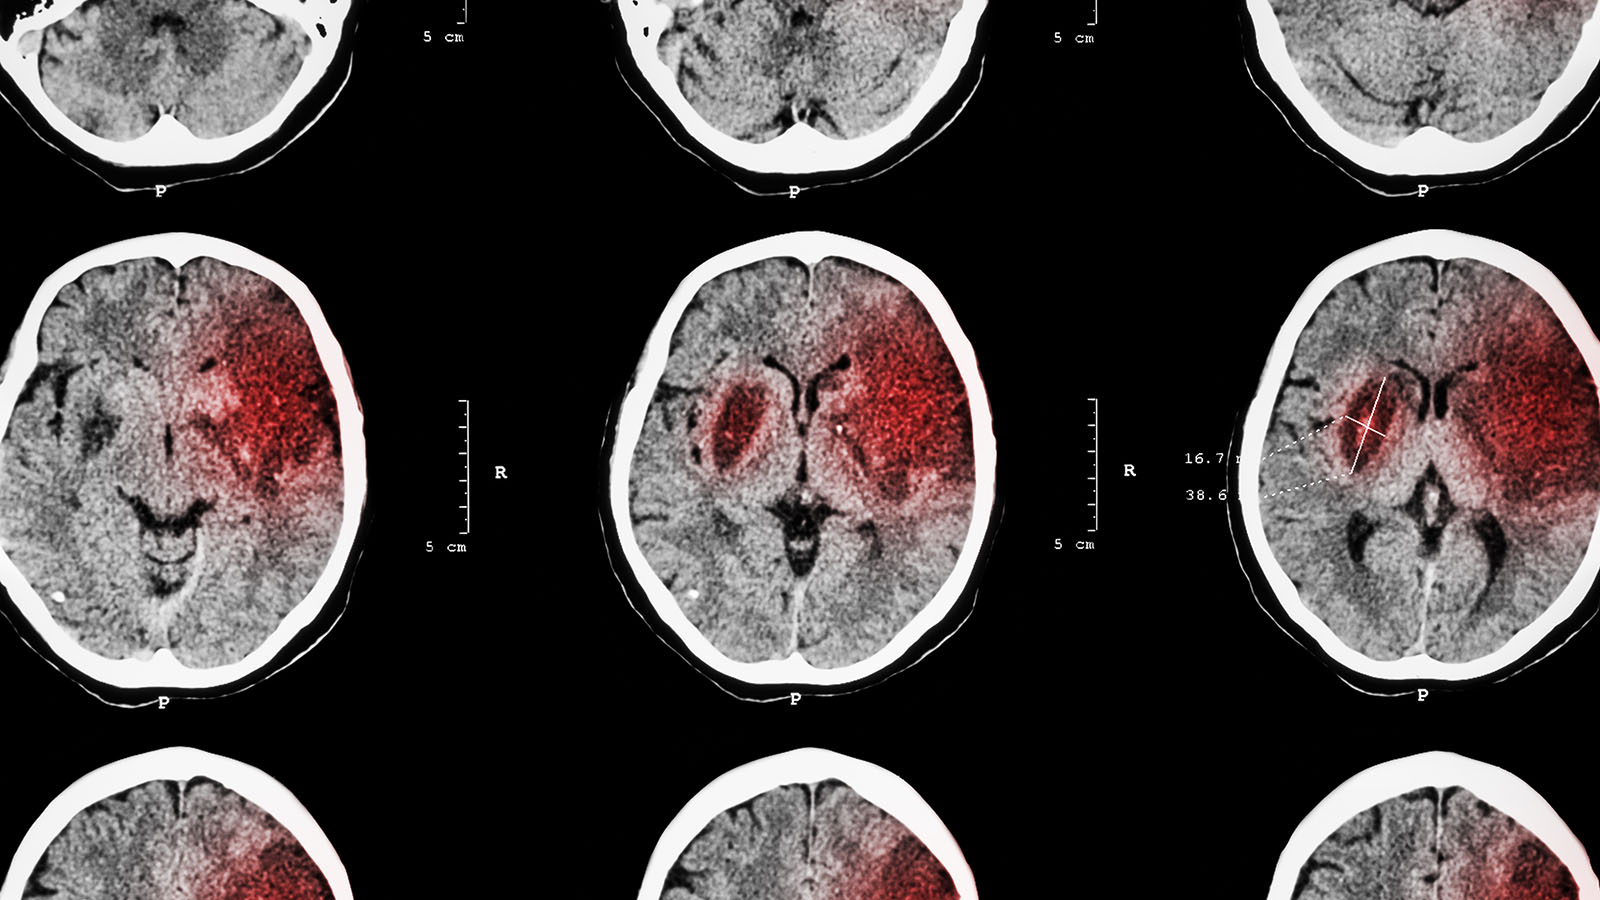

Scientists at Stanford Medicine recently observed that some mice recovered from strokes better than others, leading them to wonder whether or not they could find evidence that specific genes played a role in recovery. They did.

What was found? “Distinct biological pathways” in the portion of the motor cortex opposite the lesion wrought by the stroke as well as pathways on the same side of lesion-affected cortex. There were 38 genes on the side of the brain impacted by the lesion associated with recovery and 74 genes opposite the lesion that were associated with recovery.